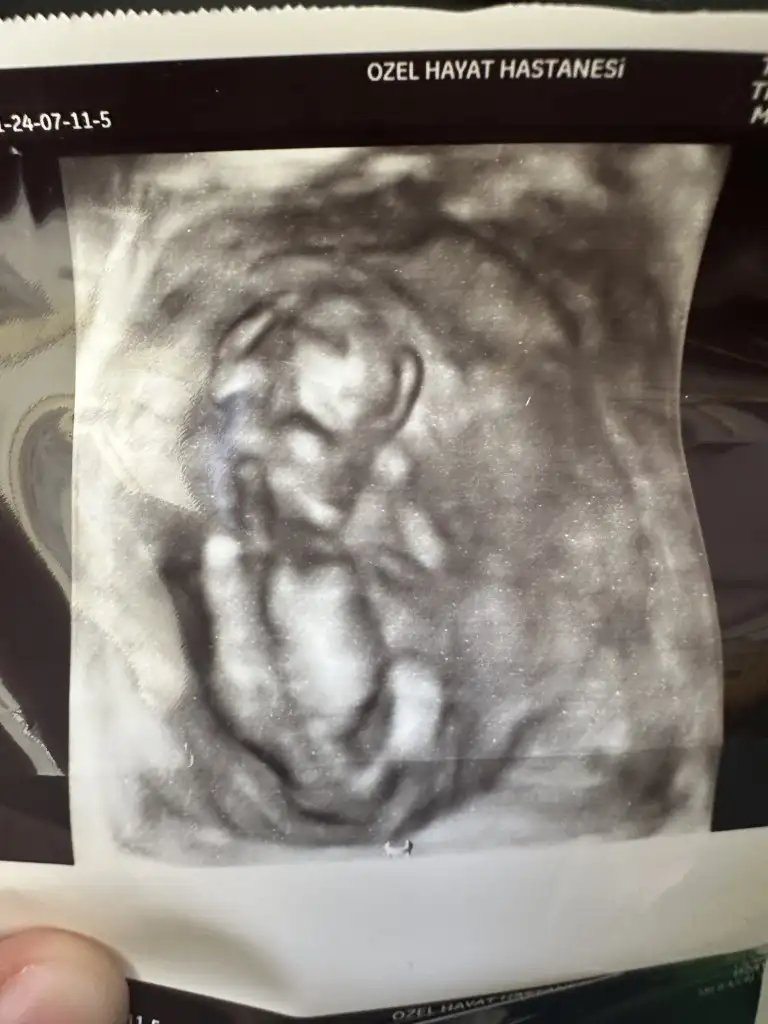

İyi Akşamlar arkadaşlar bende klübe yeni katıldım 13 haftalık bebegim anlayan arkadaşlar cinsiyetine bakabilirmi doktor kız benziyor dedi ama net birşey söylemedi

Allah gönlünüze göre versin inşallah bana da yüzde 70 kız gibi dedi bu cumartesi gidince net belli olacak 3 kızım var buda erkek olsa fena olmaz ama kız gibi geliyor bana da hayırlısı olsun tabi öncelikle sağlıklı olması 🥰